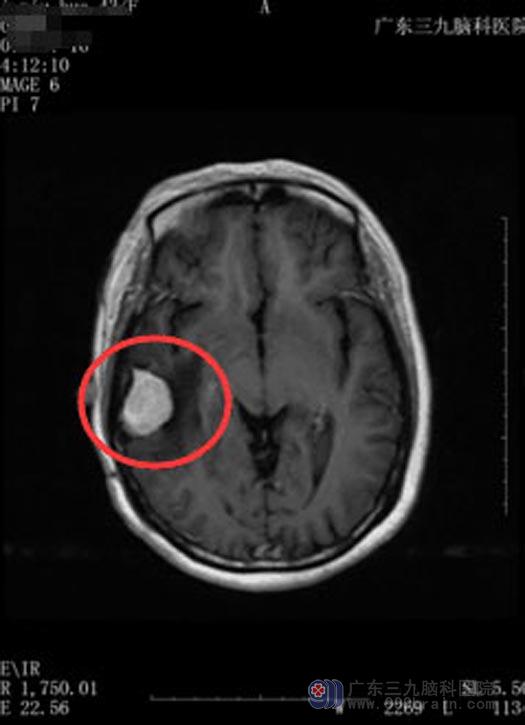

在朋友的建议下,他们来到了广东三九脑科医院。头颅CTA检查显示:右侧颞顶部内骨内板下占位病变伴较多钙化,其内见少许小血管,考虑脑膜瘤的可能性较大。

鲁明主任主刀在全麻下行“右侧颞部占位病变切除术”,导航准确定位,术中见病变组织成灰褐色,质软,边界清晰,血供丰富;顺利地将肿瘤分块切除。

手术前